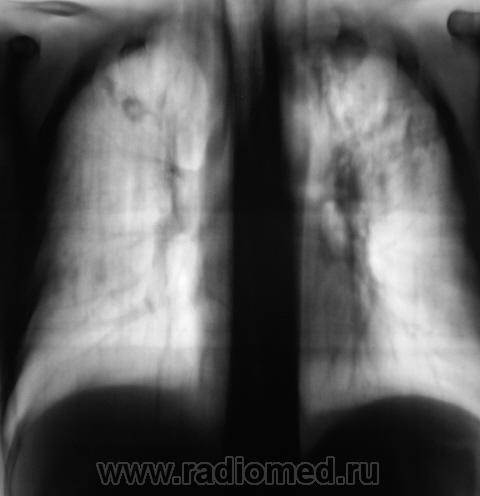

Произведено дообследование согласно стандарту.

Флюорограмма за 2007 год была оценена, как "норма". Изображение 2008 года - было отмечено локальное снижение прозрачности легочной ткани на уровне 2 ребра справа, на фоне чего дифференцируются отдельные очаговоподобные тени. Была рекоменндована "консультация терапевта" и полное клиническое обследование. Однако "сие" - рекомендации рентгенолога не были приняты к сведению.

Из беседы с "дамой" стало известно, что в последнее время - "подкашливает", откашливает некоторое количество мокроты, отмечает, что в последнее время "ослабла" и потеет по ночам. "Дама" средних лет, ведет "свободный образ жизни", уважает выпить "в меру" в "своей компании", любит мужчин, и все, что с ними связано. В настоящее время, по череди, сожительствует с двумя, хотя раньше любила другого (2 года тому), но тот умер от "геркулеса".